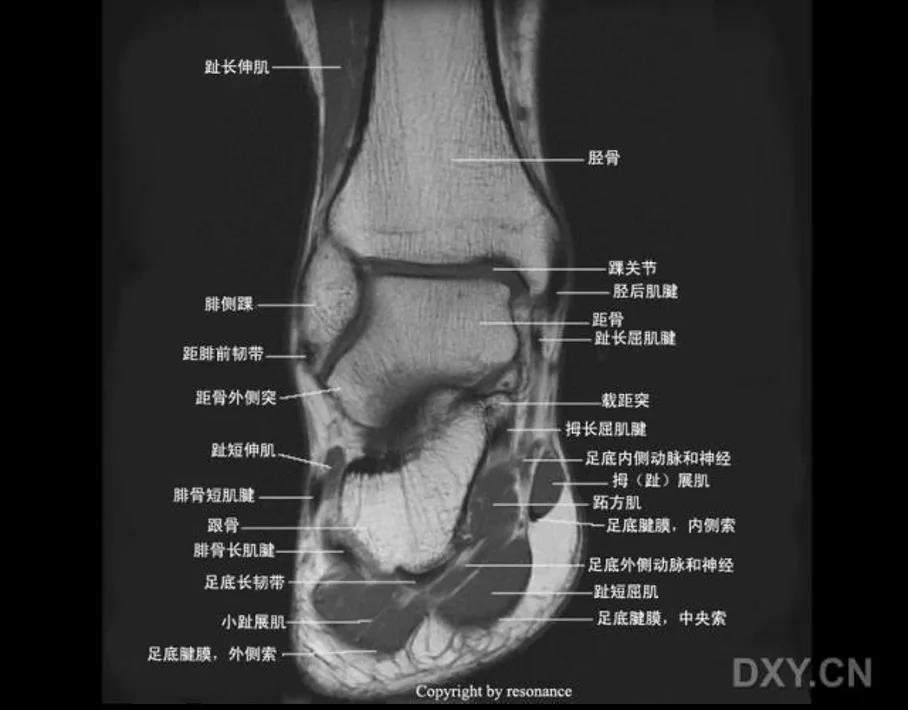

MRI: